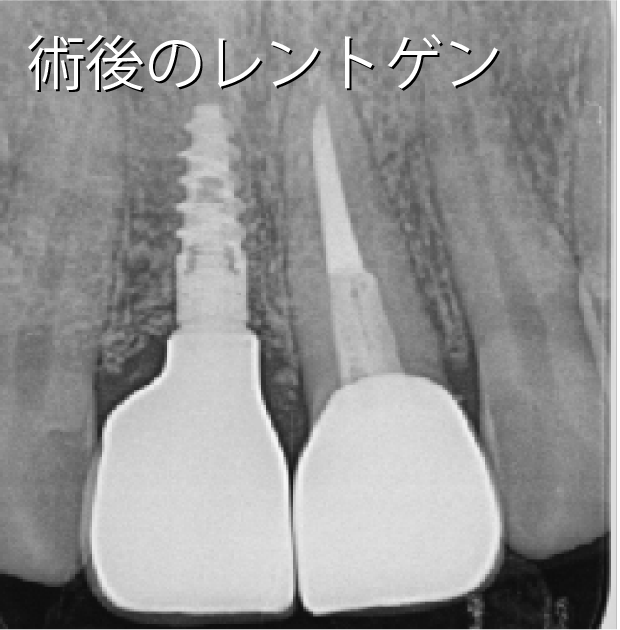

- 性別年齢

- 男性:30歳

- 治療内容

- 上顎の前歯1本をインプラント

- 金額

- 44万円(税込)

- 来院理由

- 昔事故で前歯を損傷して治療してもらったが、もっと綺麗に治せるなら、より良い治療を受けたいと思い、カウンセリングに来た。

- 施術の

副作用

(リスク) - 経過とともになくなりますが、術直後に腫れや違和感を感じることがあります。